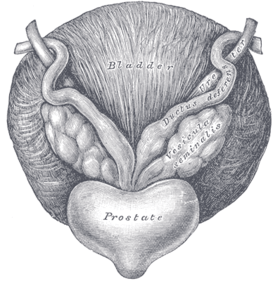

Prostate with seminal vesicles and seminal ducts, viewed from in front and above. | |

Fundus of the bladder with the vesiculæ seminales. Vesiculae seminales and ampullae of ductus deferentes, front view.

Vesiculae seminales and ampullae of ductus deferentes, front view. Vertical section of bladder, penis, and urethra.